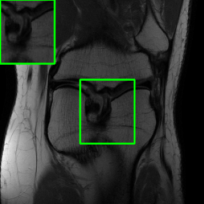

In Fig. 1-(a) and (b), we show reconstructed images using MoDL originating from a benign (i.e., undisturbed) input and a PGD scheme-perturbed input, respectively. It is evident that the worst-case input disturbance significantly deteriorates the quality of the reconstructed image. While one focus of this work is to enhance robustness against input perturbations, Fig.1-(c) and (d) highlight two additional potential sources of instability that the reconstructor (MoDL) can encounter during testing: variations in the measurement sampling rate (resulting in “perturbations” to the sparsity of the sampling mask in ) [20] and changes in the number of unrolling steps [22]. In scenarios where the sampling mask (Fig.1-(c)) or number of unrolling steps (Fig.1-(d)) deviate from the settings used during MoDL training, we observe a significant degradation in performance compared to the original setup (Fig.1-(a)), even in the absence of additive measurement perturbations. In Section IV, we demonstrate how our method improves the reconstruction robustness in the presence of different types of perturbations, including those in Fig.1.

Table II compares image reconstruction quality with different methods at two sampling acceleration factors for the knee dataset. We observe quite similar and congruous outcomes to those reported in Table I. Figs. 6 and 7 show reconstructed images by different methods for knee scans at 4x and 8x undersampling, respectively. We observe that SMUG and Weighted SMUG show fewer artifacts, sharper features, and fewer errors when compared to Vanilla MoDL reconstruction in the presence of the worst-case perturbations.